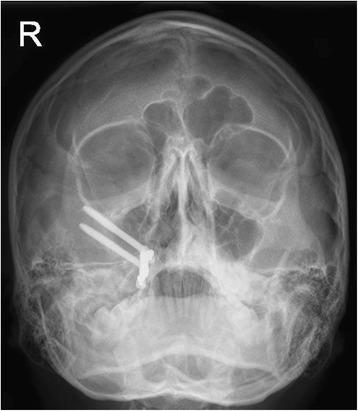

This report details the use of zygomatic oncology osseointegrated implants to support and retain a maxillary obturator in a 13-year-old male patient who underwent a right-sided hemi-maxillectomy (Brown Class 2b) (Brown and Shaw, Lancet Oncol 11:1001-8, 2010) for a myxoid spindle cell carcinoma. At the time of maxillary resection, two zygomatic oncology implants were inserted into the right zygomatic body and subsequently utilised to provide in-defect support and retention for a bar-retained maxillary acrylic obturator prosthesis, which restored the patient's aesthetics and function to a very high level. Close follow-up over 2 years demonstrated ongoing excellent function and disease control with no deleterious effects on facial or dento-alveolar growth clinically. This is the first clinical report of its kind in the published literature detailing the use of a zygomatic implant-retained obturator in a paediatric patient.

本报告详细介绍了在一名13岁男性患者中使用颧骨肿瘤骨整合种植体来支撑和固定上颌阻塞器的情况。该患者因黏液样梭形细胞癌接受了右侧半上颌骨切除术(Brown 2b级)(Brown和Shaw,《柳叶刀·肿瘤学》11:1001 - 8,2010年)。在上颌骨切除时,将两枚颧骨肿瘤种植体植入右侧颧骨体,随后用于为杆式固定的上颌丙烯酸阻塞器假体提供缺损内支撑和固定,该假体将患者的美观和功能恢复到了很高水平。超过2年的密切随访显示,功能持续良好且疾病得到控制,临床上对面部或牙牙槽骨生长无不良影响。这是已发表文献中首例详细介绍在儿科患者中使用颧骨种植体固定阻塞器的临床报告。